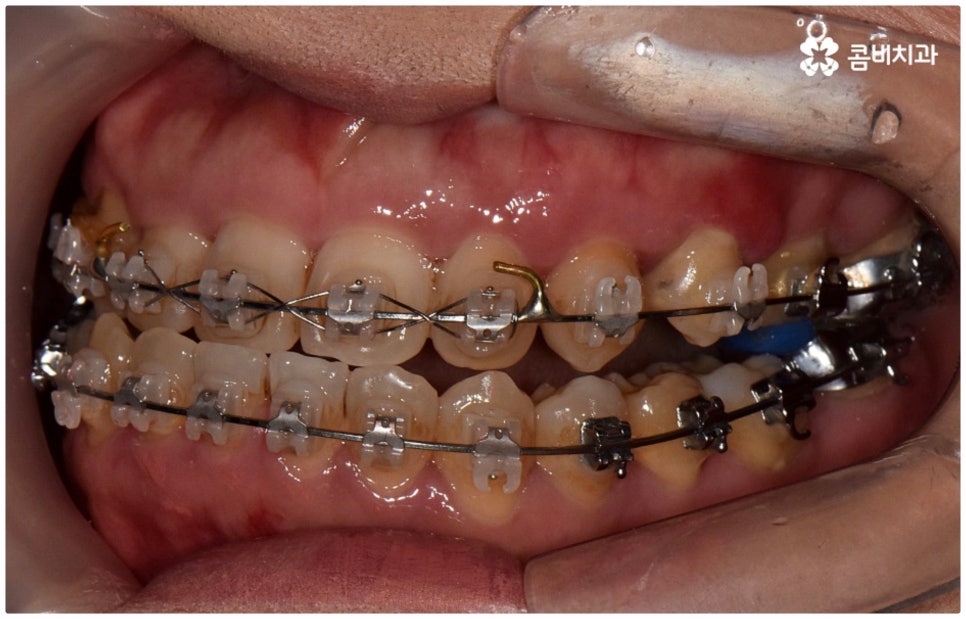

출처 아카이브 열기위아래 치열이 제대로 맞물리지 않으면 음식물을 씹을 때 어려움을 느끼거나 발음상 문제가 생길 수 있습니다. 이것을 부정교합이라고 하며, 그 종류는 상악과 하악의 골격적인 전후방 관계를 기준으로 1급, 2급, 3급으로 나눌 수 있어요. 위아래 어금니는 잘 맞물리는데 치열이 조금씩 삐뚤어져 있거나 치아 사이가 벌어져 있는 등 살짝씩 어긋난 부정교합은 1급, 위 어금니가 더 앞으로 나가있는 부정교합은 2급 (ex. 돌출입), 그리고 아래 어금니가 더 앞으로 나가있는 부정교합은 3급 (ex. 주걱턱) 으로 분류하게 되는데 이 중 오늘 살펴보려고 하는 것은 부정교합 3급에 해당하는 반대교합에 대한 거예요.

정상적인 교합은 윗 앞니가 아래 앞니를 살짝 덮는 정도로 윗니가 조금 더 앞으로 나와 있으면서 위아래 치아가 어금니까지 잘 맞물리는 것을 말하는데 반대교합은 위아래 앞니가 거꾸로 물리는 증상을 보이기 때문에 저작 활동 및 발음 조성이 원활하지 않게 되며 반대교합교정 등 적절한 치료를 받지 않고 방치할 경우 점점 더 주걱턱이 강화되는 쪽으로 뼈가 성장할 수 있어 될 수 있는 대로 빠른 시일 내에 원인을 분명하게 알아보고 그에 맞는 치료를 받는 것이 중요하다고 할 수 있어요.

골격적인 원인이 아니라면 위턱과 아래턱의 위치나 크기에는 이상이 없는데 치아의 맹출 각도 및 방향의 문제로 인해 치아가 반대로 맞물리게 된 치성 반대교합에 해당하는 경우라고 할 수 있는데요. 그 원인으로는 선천적인 치열의 문제 (아래턱 앞니 치축이 앞으로 기울거나 위턱 앞니 치축이 뒤로 들어감), 유치가 너무 빨리 빠지고 영구치가 자리를 제대로 잡지 못해 생긴 문제, 후천적인 습관 (혀를 내밀거나 손톱을 깨무는 등 치열에 좋지 않은 영향을 주는 행위를 지속적으로 반복) 으로 인한 문제 등등을 살펴볼 수 있으며, 보통 이런 경우 앞니 4~6개 치아 일부에 국한된 문제이기 때문에 보다 빠르고 간단하게 교정 치료가 가능하므로 꼭 성장기에 치료를 시작하지 않고 성인이 된 후라고 해도 비교적 쉽게 개선이 될 수 있습니다.

반대교합의 경우 보통 두 원인이 혼재되어 나타나는 경우가 많으며 또한 환자분들의 상황에 따라 정확한 치료가 달라지기 때문에 꼼꼼한 검진 후 각자에 맞는 반대교합교정 치료를 통해 이를 바로잡아 주시길 권유드리고 있어요. 검진과 치료를 받을 때는 3D CT와 같은 정밀 검사 기계를 갖추고 있는 치과에서 임상 경험이 풍부하고 뛰어난 노하우와 기술을 가지고 있는 숙련된 의료진에게 반대교합교정 치료를 진행하는 것이 좋을 거예요.

교정 치료가 생물학적 반응을 이용하는 것이다 보니 성장기에 진행하면 치아 이동 및 회복 속도 등에 장점이 있는 것은 분명하지만 그렇다고 해서 성인 이후 중장년 분들이 교정 치료를 받을 수 없는 것은 아니며 이미 많은 분들이 도움을 받고 계신 만큼 이에 대해서 한 번 고려해 보시면 좋을 거예요. 혹시 성장기 이후로는 양악 수술 등으로만 치료가 가능한 것이 아닐까 생각하셔서 부담스럽게 느끼셨던 분들이라면 지레 겁을 먹고 불편함을 그대로 방치하시기 보다는 검진 및 상담을 통해 적극적으로 이를 해결해 보시길 권유드리고 있어요.

물론 원인과 정도에 따라 외과적인 방법이 필요하신 분들도 있을 수 있지만 교정을 통해 얼마든지 치료가 가능한 경우도 있으며 앞서 말씀드렸던 것처럼 발전된 교정 기술 및 특수 미니스크류 등의 장치 개발을 통해 턱의 방향을 조금씩 회전시켜 원거리 치아 이동을 유발하는 것이 가능해졌기 때문에 예전에는 한계가 있었던 부정교합 케이스도 개선될 여지가 늘어나고 있습니다. 꼼꼼하게 검진을 받으시고 자신의 상황에 맞는 교정 치료를 무리하지 않게 진행하신 후 철저하게 사후 관리를 해주시면 보다 오랜 기간 동안 건강하게 고른 치열을 유지하면서 생활하실 수 있을 거예요.